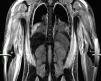

Caso clínicoNiño de 7 años, previamente sano, con una historia de 4 semanas de evolución de fiebre, eritema facial y angioedema, que se trató con corticoides orales y antihistamínicos. Posteriormente, requirió hospitalización por edema facial, cervical, dolor y debilidad muscular, solicitándole traslado a la UCI por inestabilidad hemodinámica a las 24h de su ingreso. A la admisión en la UCI se observó al paciente con una puntuación de Glasgow de 10, Tª 38,3°C, frecuencia cardiaca 160 latidos por minuto, presión arterial media 50mmHg y tiempo de llenado capilar de 5 segundos. Edema facial y de extremidades, heliotropo periorbitario, adenopatía cervical derecha, vasculitis en la zona glútea, con lesiones de pequeño vaso en zona periungueal. El abdomen era sensible difusamente, con hepatoesplenomegalia. Se observó debilidad muscular proximal en las extremidades. La evaluación por el reumatólogo pediatra planteó el diagnóstico de DMJ y SAM secundario. En los exámenes de ingreso destacaron: pH 7,1, EB –9,6, lactato 4.6mmol/l, sodio 129 mEq/l, proteína C reactiva 0,5mg/dl y hallazgos de laboratorio compatibles con SAM y actividad de DM (tabla 1). La ecografía cardiaca demostró una fracción de acortamiento de ventrículo izquierdo del 20%. Se inició tratamiento con volemización, ventilación mecánica, infusión de dobutamina, noradrenalina y antibióticos de amplio espectro. Evolucionó con FMO, insuficiencia respiratoria grave (Pa/FiO2= 80), lesiones purpúricas y anasarca. Los hemocultivos y los cultivos de aspirado bronquial fueron negativos, así como la serología para Mycoplasma pneumoniae, hantavirus y virus de la inmunodeficiencia humana, y la reacción en cadena de la polimerasa para virus de Epstein-Barr, citomegalovirus, parvovirus B19 y enterovirus. La IgM para virus de la hepatitis A y B fue negativa. La inmunofluorescencia directa de aspirado nasofaríngeo para virus influenza, parainfluenza, sincitial, adenovirus y metaneumovirus fue negativa. Los anticuerpos antinucleares fueron positivos. La RM de las extremidades en secuencia STIR (short tau inversion recovery) reveló edema difuso subcutáneo, muscular y de la fascia (fig. 1). La biopsia muscular demostró infiltrados inflamatorios perifasciculares con fibras necróticas y signos de vasculitis inicial. El aspirado de médula ósea fue normal y no fue repetido posteriormente por la condición del paciente. El estudio de citotoxicidad demostró ausencia de citotoxicidad de las natural killer (NK). Al ingreso, se iniciaron bolos de metilprednisolona de 1 g/kg/día por 5 días e infusión de inmunoglobulinas 2 g/kg y en las 24h siguientes se agregó al tratamiento ciclosporina por vía intravenosa 5mg/kg. Sin embargo, el paciente se mantuvo febril, dependiente de fármacos vasoactivos, e inició signos de compromiso encefálico, derrame pleural bilateral y hemorragia de mucosas. La tomografía de cerebro fue normal. Por evolución desfavorable, al cuarto día se inició PF a través de un catéter femoral de doble lumen con un sistema de centrifugación a flujo discontinuo (Haemonetics MCS 8150 Massachusetts, EE. UU.). El procedimiento fue programado para remover una volemia por sesión, usando como solución de remplazo plasma fresco congelado. Después de 4 sesiones de PF, se observó una resolución del FMO, lográndose una suspensión de los fármacos vasoactivos y una disminución sostenida en los parámetros biológicos de actividad de la DMJ y el SAM. Se realizaron 8 sesiones de PF (tabla 1). El procedimiento no presentó complicaciones técnicas y fue bien tolerado por el paciente, que requirió 8 días de ventilación mecánica y fue egresado del hospital al día 21. Actualmente, el niño no presenta secuelas y se encuentra en buenas condiciones funcionales, ya que en la prueba MMT (muscular manual testing) presenta un valor de 88. Sus exámenes de laboratorio son normales y recibe tratamiento con prednisona.